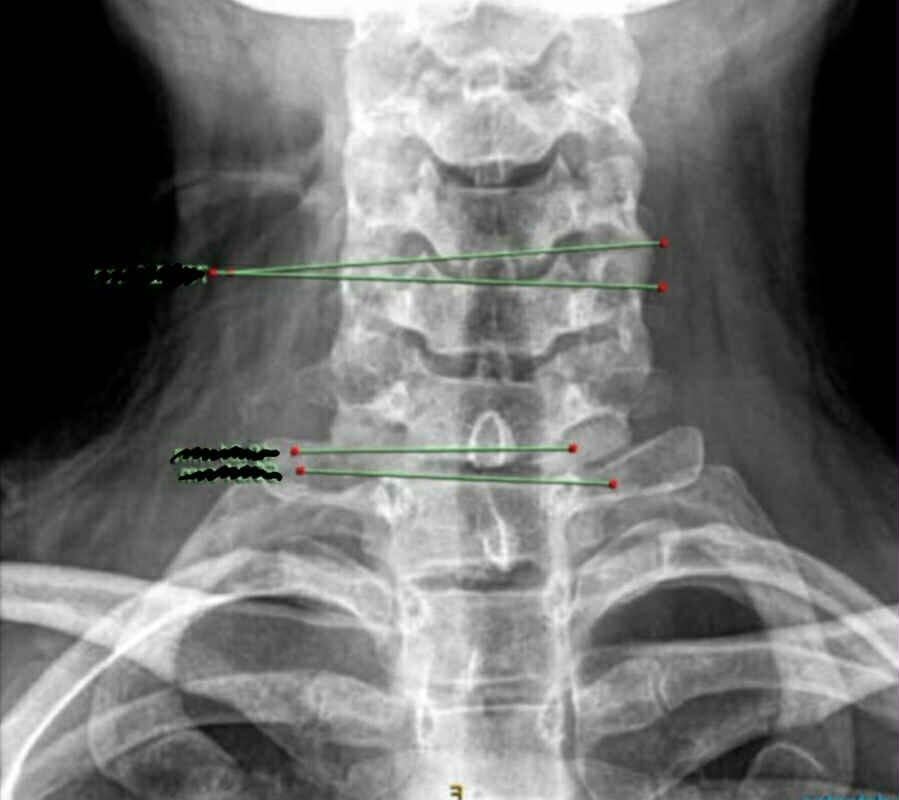

He diagnosed her with something known as significant subclavian artery compression.

"The right subclavian artery, which is the highway where all the nerves and arteries that supplies, oxygen and blood into your hand is being basically crushed between my muscles and rib," Lynch explained.

Lynch said she needs thoracic outlet decompression, a "highly specialised" surgery which involves removing a muscle and a part of the first rib to relieve compression.